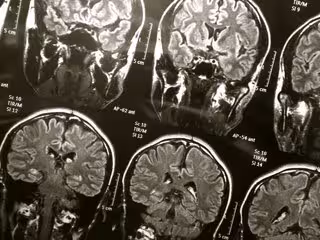

Nuevo método rápido para diagnosticar conmociones cerebrales en atletas jóvenes - FLICKR/WYINOUE - Archivo